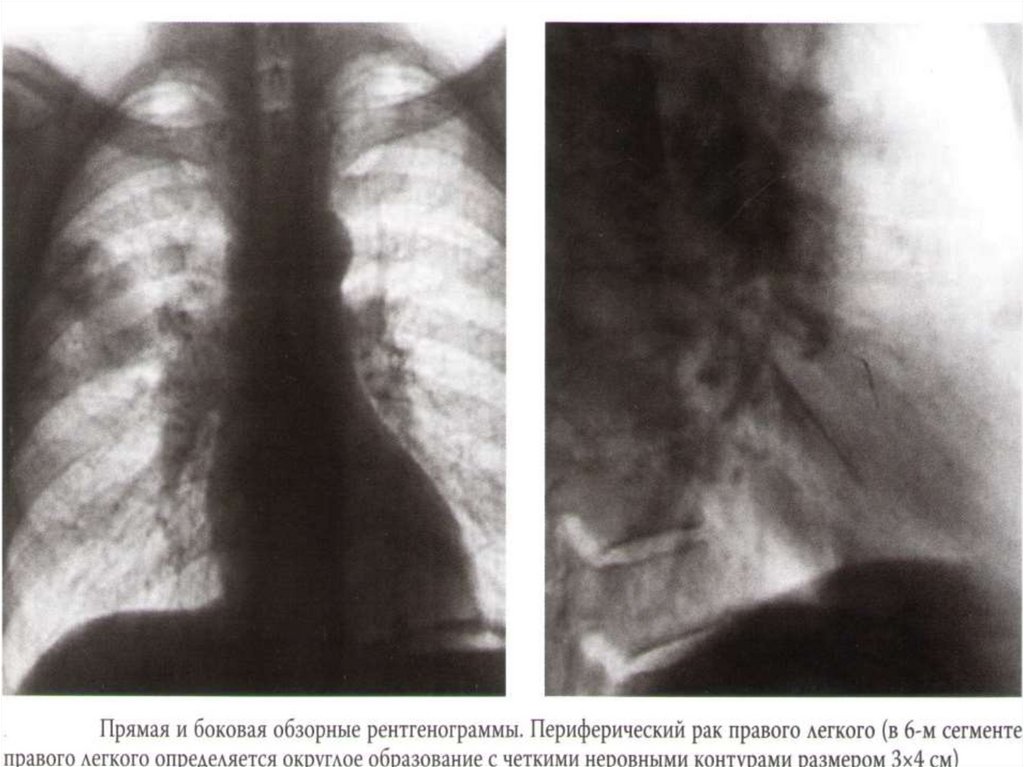

Периферический рак легкого

Боль в груди

Кашель

Одышка

Клиника абсцесса легкого (при распаде опухоли).